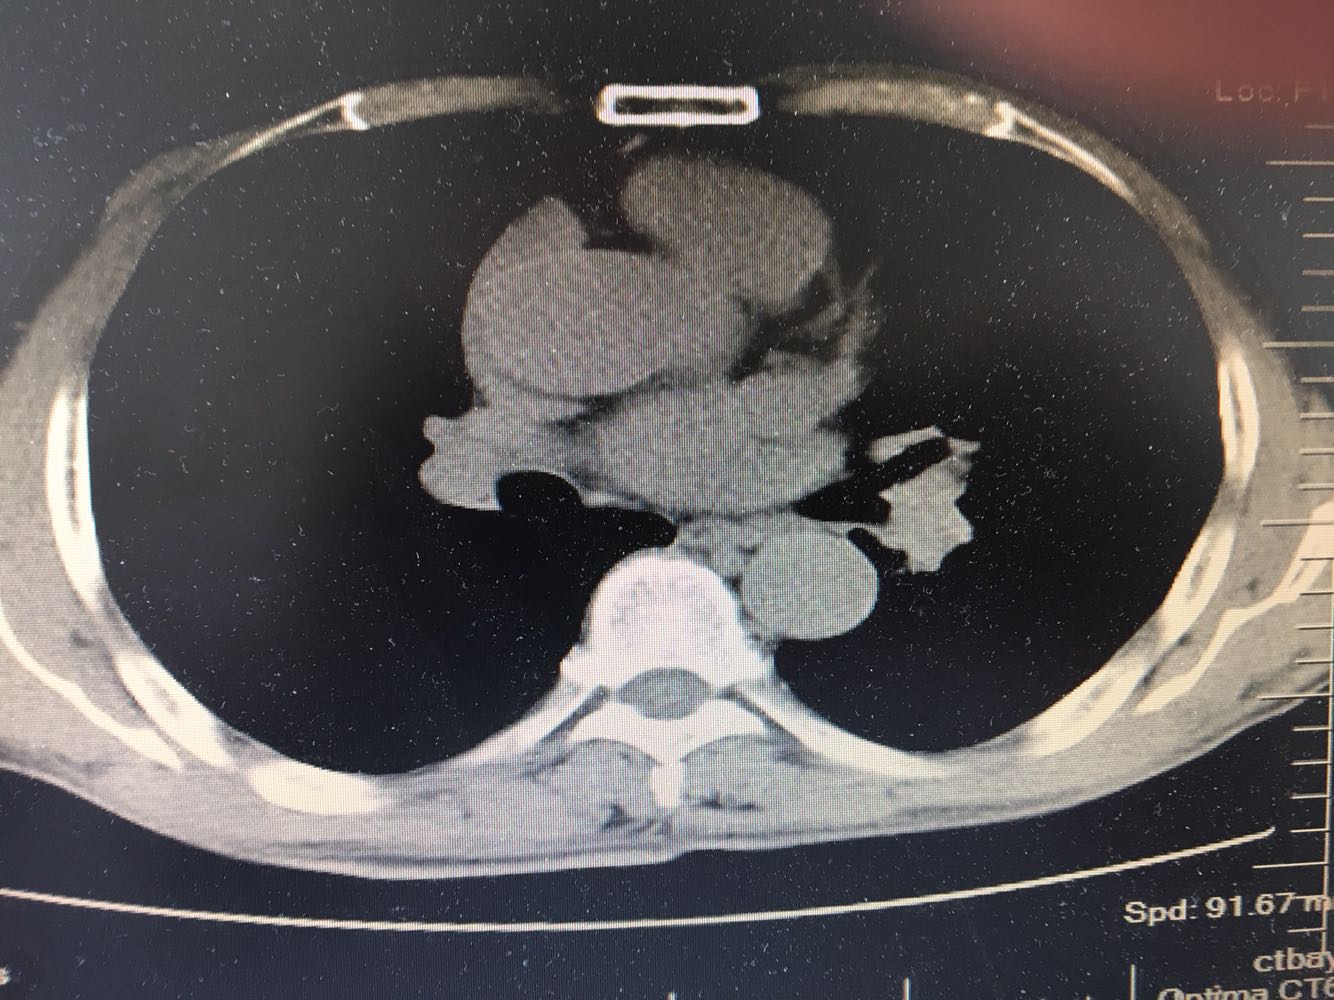

男,63岁,咳嗽1个月入院,患者自述1个月前无诱因咳嗽,阵发性干咳,无痰,时有血丝,无发热,左胸痛,活动后气短,静滴头孢13天无好转,门诊查肺CT后以 肺占位收入我科,病来饮食睡眠可,体重明显下降。既往疝气术后1年,吸烟史30年,每日1包。

左肺癌

左肺中央型肺癌,是否可以手术,还是化疗,放疗,靶向治疗?